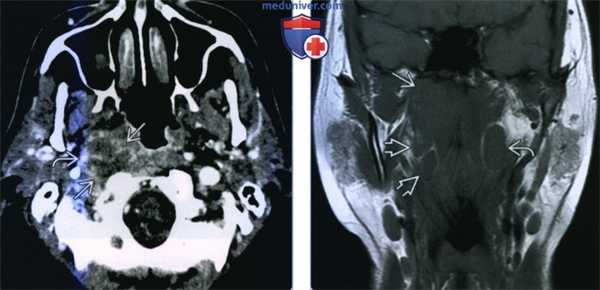

(Слева) КТ с КУ, аксиальная проекция. Метастазы плоскоклеточного рака в лимфатические узлы добавочной цепи на уровне IIB. Обратите внимание, что лимфоузлы находятся кнутри от грудино-ключично-сосцевидной мышцы и кзади от внутренней яремной вены. Также видны лимфоузлы уровня IIА, но они не относятся к добавочной цепи. Наличие центрального некроза придает лимфоузлам кистозный вид.

(Справа) КТ с КУ, аксиальная проекция. Лимфоузлы добавочной цепи интенсивно накапливают контрастное вещество (уровень IIВ, глубже грудино-ключично-сосцевидной мышцы и кзади от внутренней яремной вены). Также видны лимфатические узлы других групп.

(Слева) КТ с КУ, аксиальная проекция. Метастазы плоскоклеточного рака в лимфоузлы добавочной цепи уровней IIВ и V. Обратите внимание, что лимфоузлы V уровня лежат точно позади грудино-ключично-сосцевидной мышцы, в то время как лимфоузлы уровня IIВ находятся сзади от нее.

(Справа) КТ с КУ, рецидив опухоли в лимфатических узлах добавочной цепи с противоположной стороны. Пациенту уже была выполнена ларингэктомия и шейная лимфодиссекция справа. Эти лимфатические узлы находятся в нижней части шеи, поскольку добавочный нерв проходит по задней поверхности заднего шейного пространства.